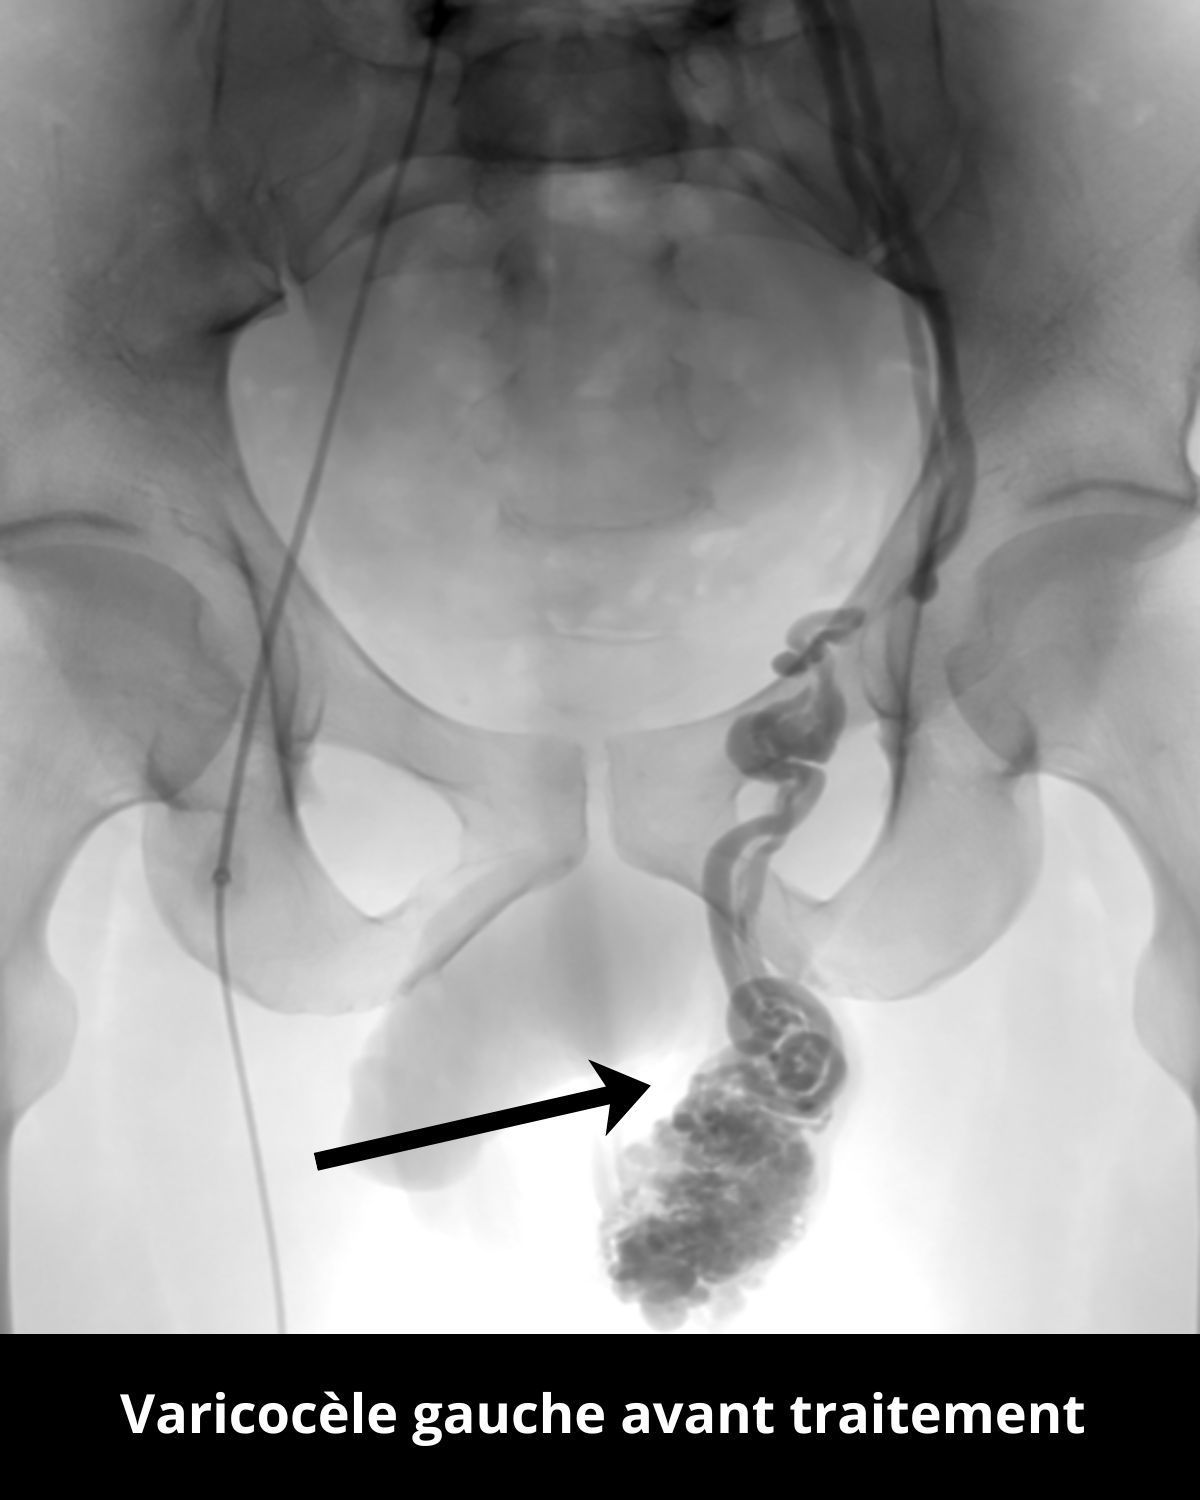

Ici le cas d’un patient consultant pour une infertilité depuis 2023.

Une petite ponction au niveau du pli de l’aine droit permet d’accéder à la veine spermatique pour la boucher de manière ciblée grâce à de la colle et des coïls, corrigeant ainsi le reflux responsable de la varicocèle.